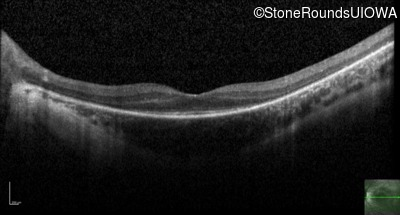

Optical Coherence Tomography - Left - 20/70

Exemplar / OCT Stack